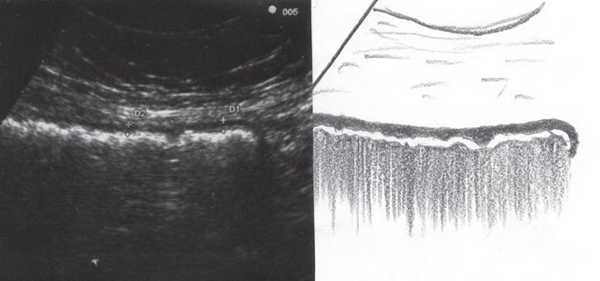

При УЗИ были выявлены диффузные изменения печени и поджелудочной железы, признаки хронического бескаменного холецистита, ангиомиолипома левой почки (без динамики за несколько лет), состояние после экстирпации матки с придатками. В левой подвздошной области соответственно зоне максимальной пальпаторной болезненности на протяжении 9 см отмечалось утолщение стенок толстой кишки до 6-7 мм (рис. 1). Перистальтика кишки отсутствовала, гаустрация была слабо выражена, при этом визуализировалось несколько болезненных при надавливании датчиком выпячиваний пониженной эхогенности, размером от 7 до 20 мм (рис. 2, а, б) с тонкой стенкой до 0,9-1,1 мм и наличием в некоторых из них фрагментов кишечного содержимого и газа (рис. 3, а, б).

Рис. 1. Эхографическая картина дивертикулита. Трансабдоминальное исследование линейным датчиком 7,5 МГц.

"Симптом пораженного полого органа".